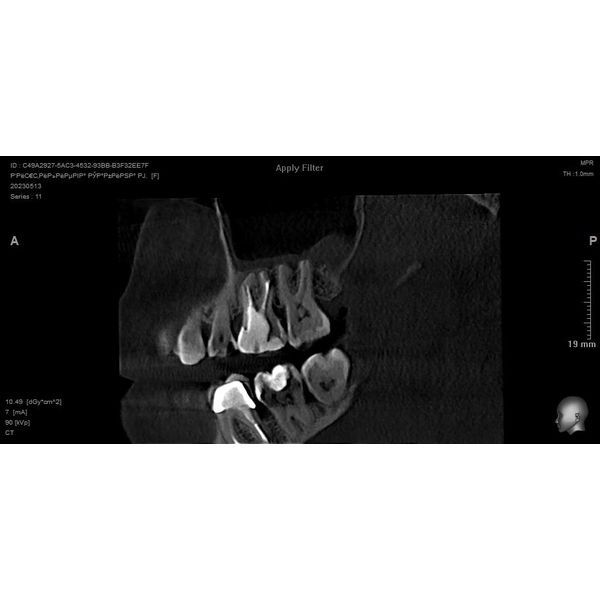

Через 2 недели поставили постоянную пломбу из герметика Adseal и гуттаперчи 2.0, после чего сделали контрольный рентген-снимок. Стекловолоконный штифт был зафиксирован в нёбном канале, культя зуба восстановлена.

Пациентку направили на повторную КЛКТ, которая показала положительную динамику, в верхнечелюстной пазухе слева восстановилась воздушность.

Женщина снова могла нормально дышать, у неё прошла боль в зубе 2.6 при накусывании и тяжесть при наклоне головы.